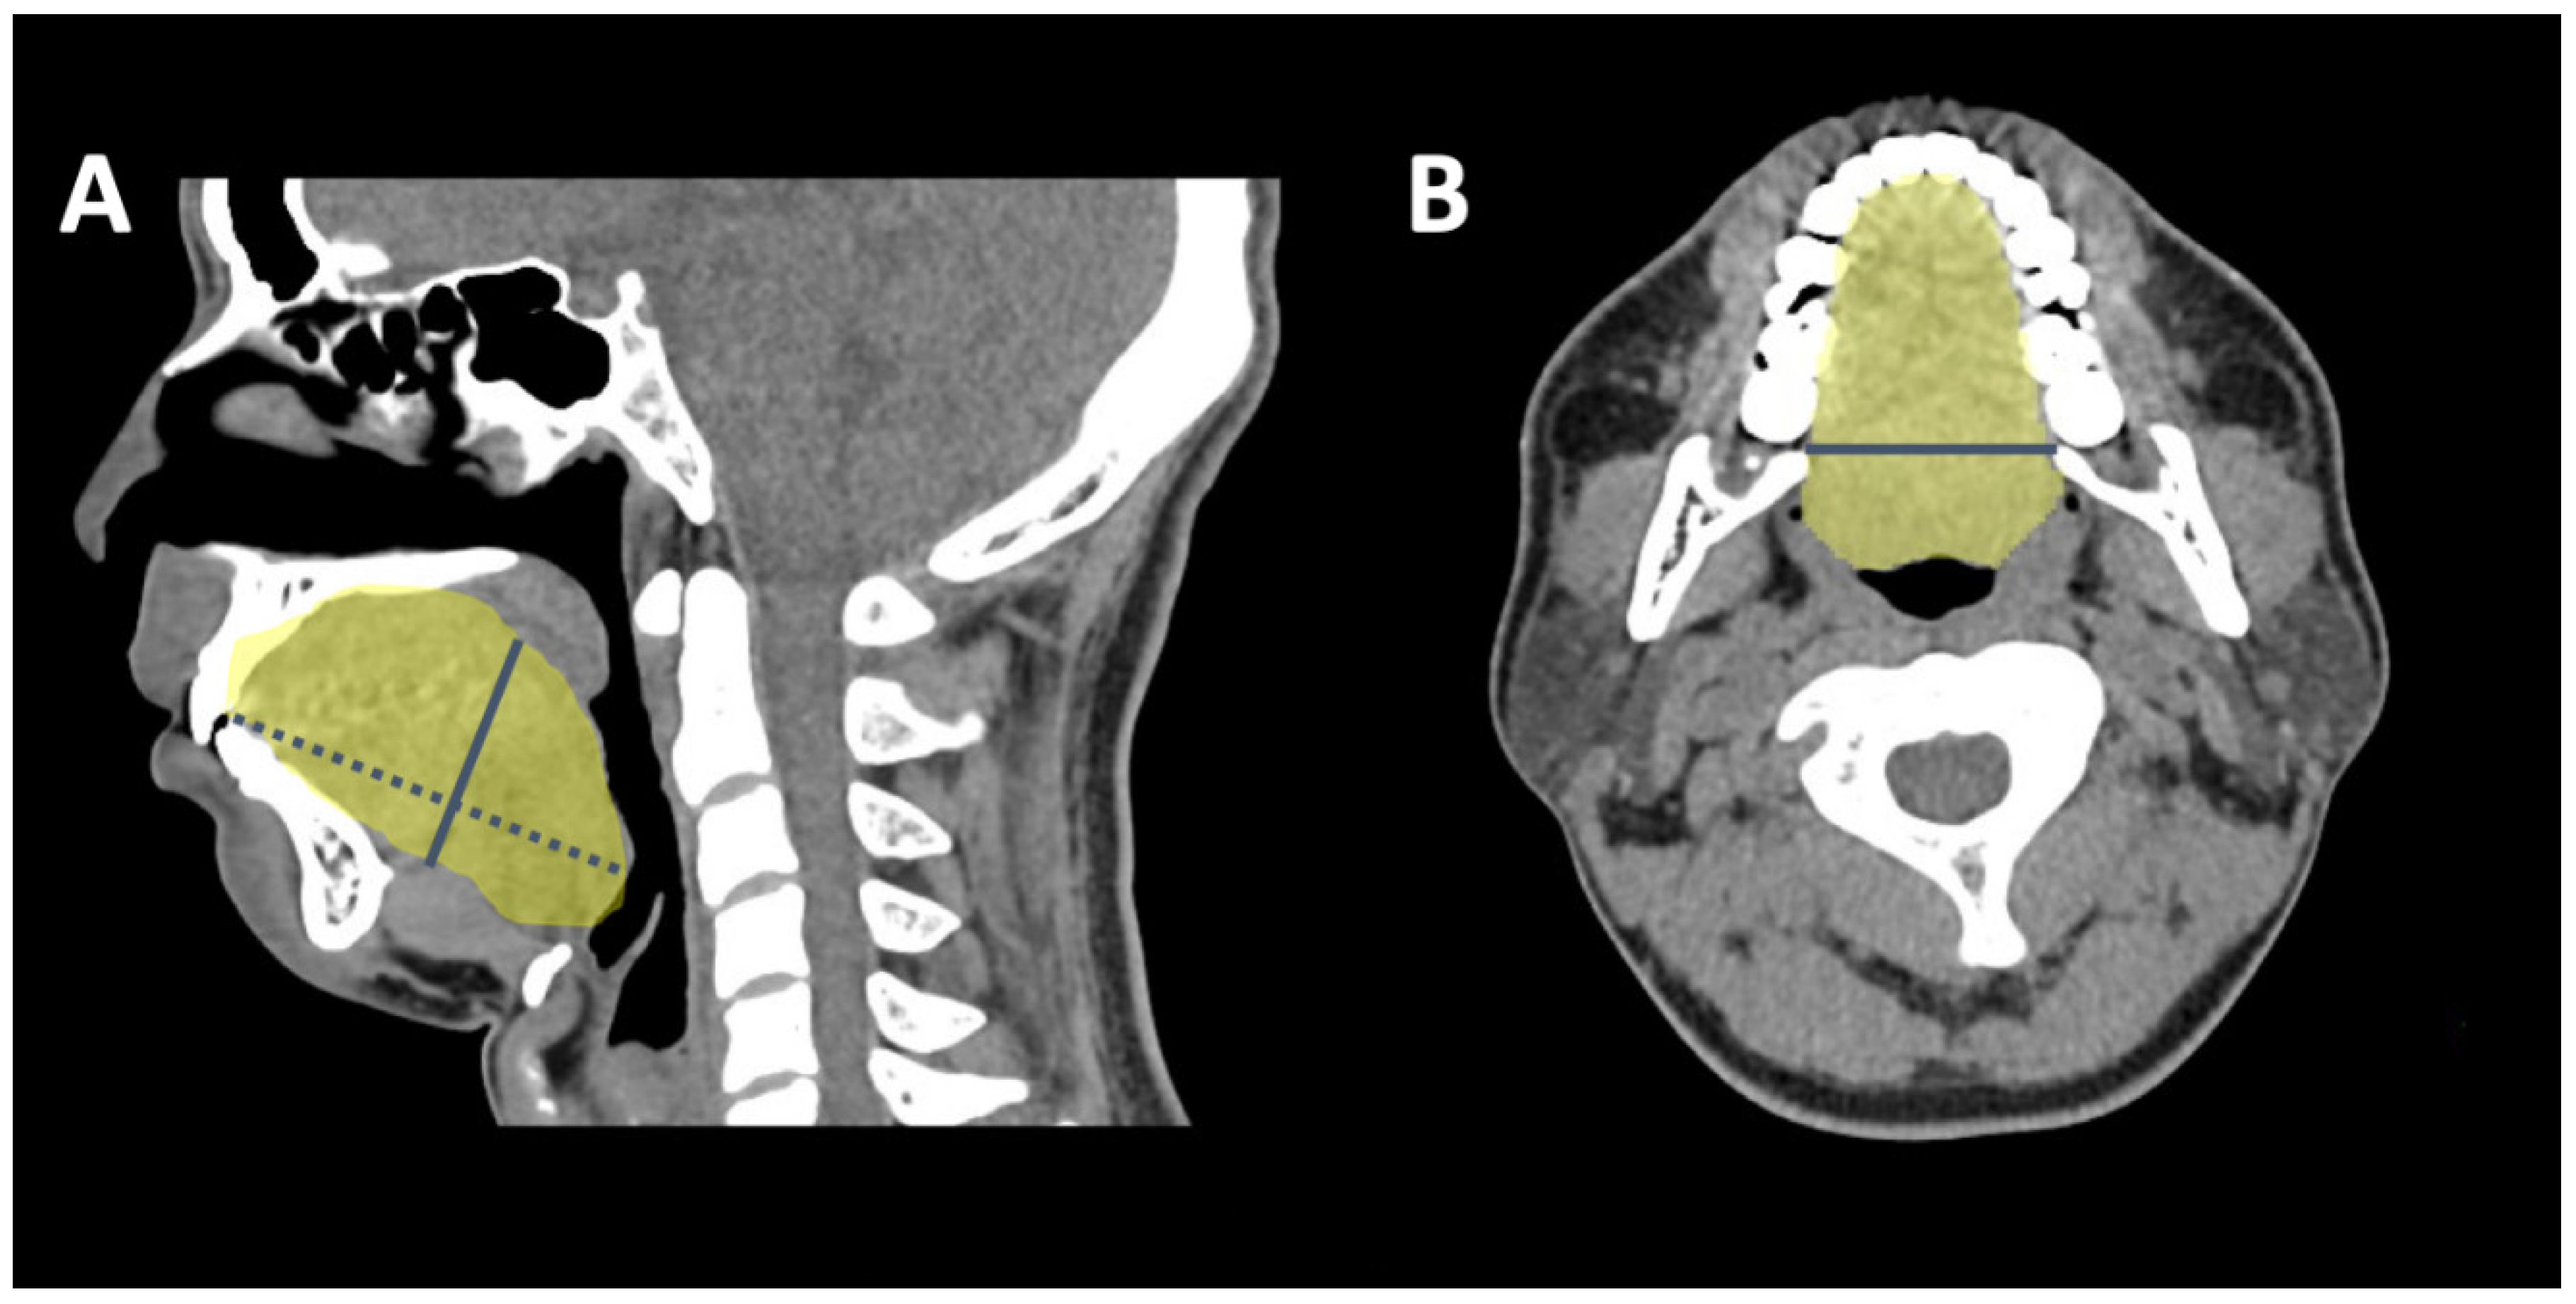

2.4. 3-D CT Measuring Algorithm

2.5. Surgical Plan and Design for Coblation Whole Tongue Surgery